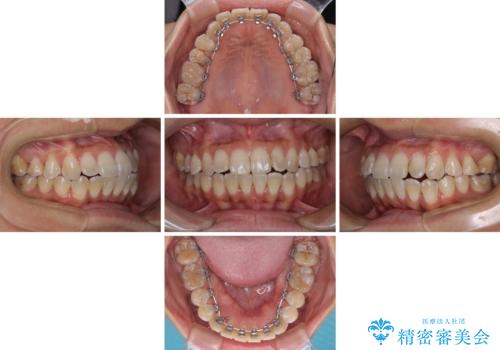

- 3年8ヶ月

- 30回以上

途中転勤や出産があり、通院できない期間が長くありましたが、無事に歯列を整えることができました。